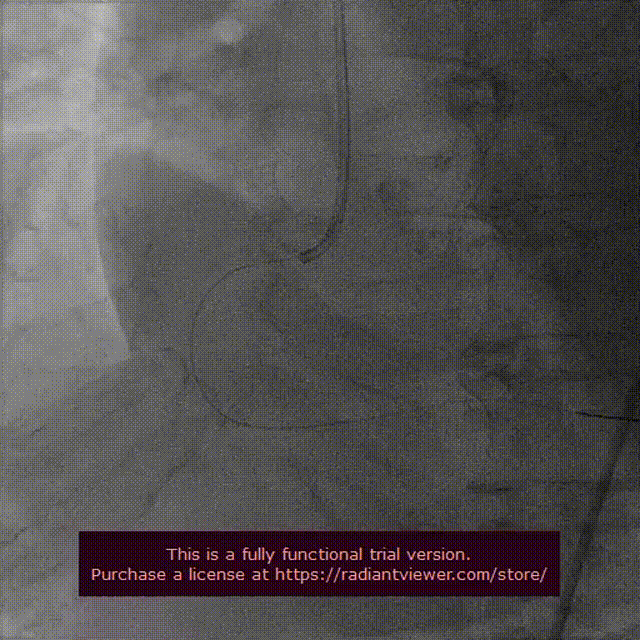

术中近75°的横位心,主动脉弓步成锐角导致输送器过弓异常困难,snare抓捕输送器胶囊腔头端,团队成员临危不乱,有条不紊,齐心协力使输送器顺利过弓。

VenusA-Plus®输送器在snare辅助下顺利过弓跨瓣,将VenusA-Plus®L26瓣膜精准定位到无冠窦最低点。